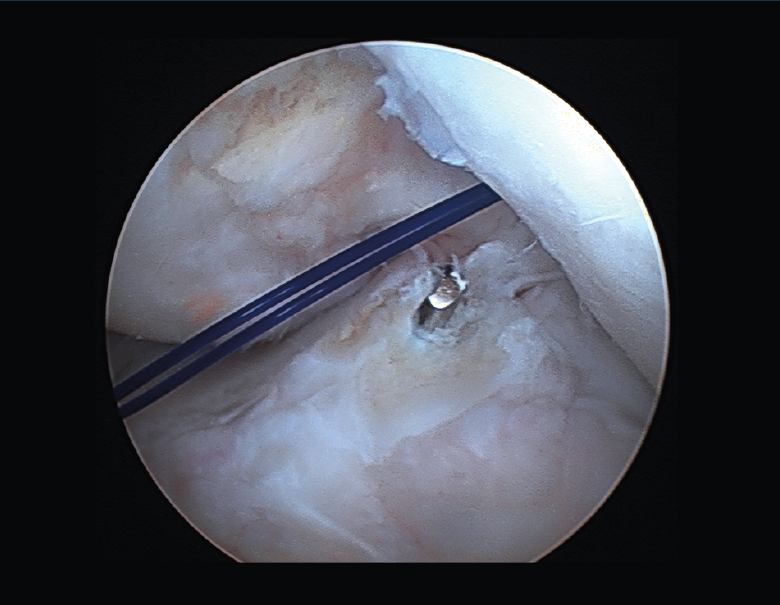

1. Túneles correctos y en buen estado. Situación ideal en la que, tras una buena limpieza artroscópica minuciosa de los túneles (Figura 20) y la retirada del tejido fibroso, procederemos al recambio simple de la plastia.

2. Túneles en posición no anatómica. En caso de tener suficiente espacio para nuestra plastia, procederemos a su sustitución con nuevos túneles en posición anatómica (Figura 21). Deberemos tener precaución para evitar el colapso del túnel previo. Si hubiera tornillo en dicho túnel y no interfiere con el nuevo túnel, se podría mantener. En caso de no estar ocupado por material, valoraremos el relleno del antiguo túnel (cilindros de injerto óseo, de sustitutivo óseo o, incluso, con un tornillo)(59).

3. Túneles cuasianatómicos, parcialmente ocupados por el material de fijación previo. Podemos realizar varios enfoques, ya que no siempre será necesario retirar los tornillos o sistemas de fijación anteriores, evitando así una pérdida ósea excesiva. Cuando nos encontremos un tornillo de material biorreabsorbible, deberemos proceder a una limpieza exhaustiva del túnel y al cambio en el sistema de fijación (suspensión cortical, por ejemplo). En caso de hallar un tornillo metálico, podemos apoyarnos en este sin necesidad estricta de retirarlo, siempre y cuando nos permita suficiente superficie de contacto óseo para la correcta integración de la plastia. En ambos casos, deberemos aplicar el concepto de “divergencia de túneles” en la creación de los nuevos túneles (Figura 22). Las nuevas guías flexibles y las brocas retrógradas outside-in son de ayuda en estos casos, ya que garantizan un punto de entrada articular deseado, pudiendo modificar posteriormente la dirección del canal óseo para evitar la comunicación de los mismos y una consecuente debilidad en la fijación de nuestro injerto. Debemos evitar el temido efecto de “cañón de escopeta”. De la misma manera, en el caso del túnel tibial, puede ser necesario su relleno con injerto óseo y el cambio de angulación de la guía tibial (medialización/lateralización del mismo).